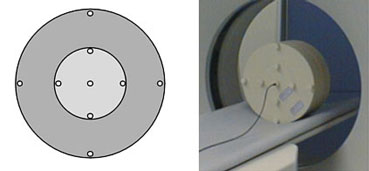

- PMMA (пластик полиметилметакрилат) фантом для головы 16см в

диаметре,

- PMMA фантом для туловища 32см в диаметре,

Фантомы для головы и туловища могут быть в двух вариантах: два отдельных цилиндра, либо как цилиндр-вставка, т. е. фантом диаметром 16 см вставляется в фантом диаметром 32 см (именно такой фантом поставлен в гг. Витебск и Гомель).

PMMA фантомы для головы, туловища и ионизационная камера производства фирмы

PTW Freiburg, Германия.

Фантом для головы и туловища в виде цилиндра-вставки.

Данные фантомы имеют отверстие в центре и 4 отверстия по периферии на 0°, 90°, 180° и 270° (отсчет из верхней точки фантома по часовой стрелке) для размещения в них ионизационной камеры.

Порядок отсчета положений ионизационной камеры (сверху по часовой стрелке).